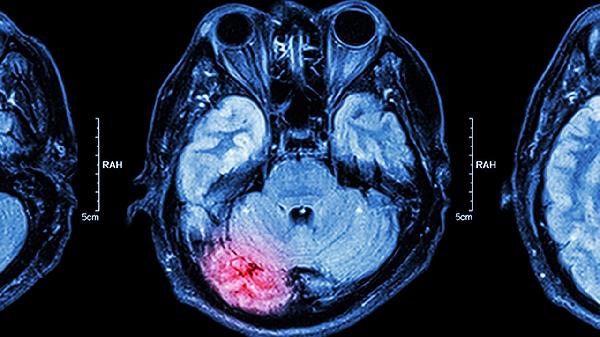

脑肿瘤患者可能会出现流鼻血,但并非典型症状。脑肿瘤的症状主要有头痛、恶心呕吐、视力障碍、肢体无力、癫痫发作等。流鼻血更常见于鼻腔局部病变或血液系统疾病。

头痛是脑肿瘤最常见的症状,通常表现为持续性钝痛或胀痛,晨起时加重,咳嗽或低头时疼痛加剧。恶心呕吐多伴随头痛出现,呈喷射性呕吐,与进食无关。视力障碍包括视物模糊、视野缺损或复视,可能与肿瘤压迫视神经或视交叉有关。肢体无力常表现为单侧肢体活动不灵活,严重时可出现偏瘫。癫痫发作形式多样,包括全身强直阵挛发作或局部抽搐,与肿瘤刺激大脑皮层有关。

流鼻血在脑肿瘤患者中相对少见,若出现可能与以下情况相关:肿瘤侵犯颅底骨质累及鼻腔血管,或长期使用抗凝药物导致凝血功能异常。但更多情况下,反复流鼻血应优先考虑鼻腔炎症、外伤、高血压或血液病等因素。脑肿瘤伴随的鼻出血通常量较大且难以止血,可能伴有其他神经系统症状。